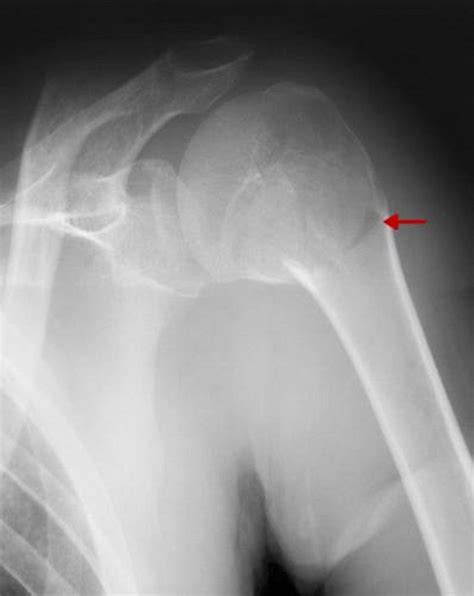

• Imaging Tests: X-rays are the primary imaging tool used to diagnose proximal humerus fractures. In some cases, additional tests such as CT scans or MRIs may be ordered to provide more detailed images.

• proximal humerus fracture radiology